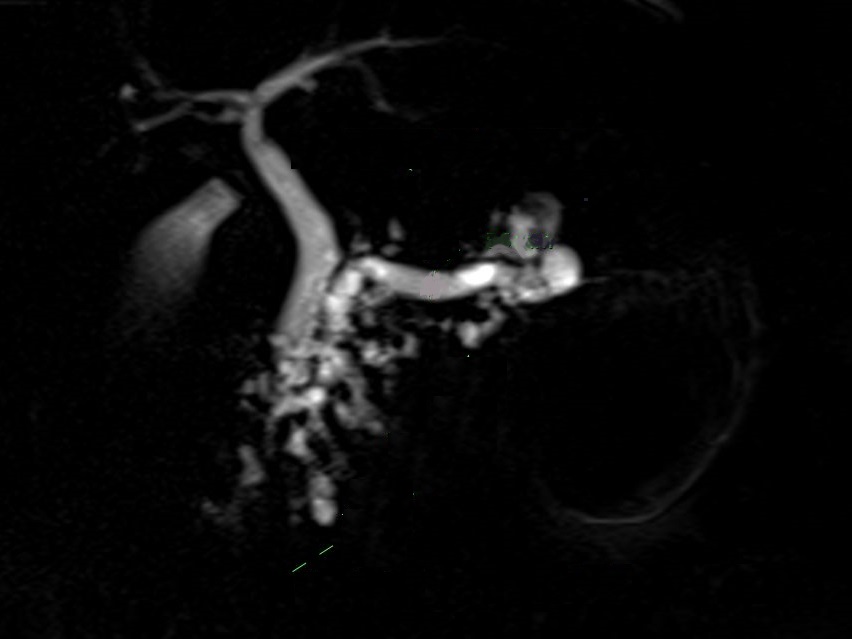

Image radiologique Wirsungo-cholangio IRM

d'une TIPMPde type canaux secondaire du corp pancreas avec image de kyste

multiple , polylobulaire ( fleche rouge ) en

communication avec la CPP . Image radiologique du

canal choledoque et des voies biliaire

intrahepatique sont en vue tres nette . |